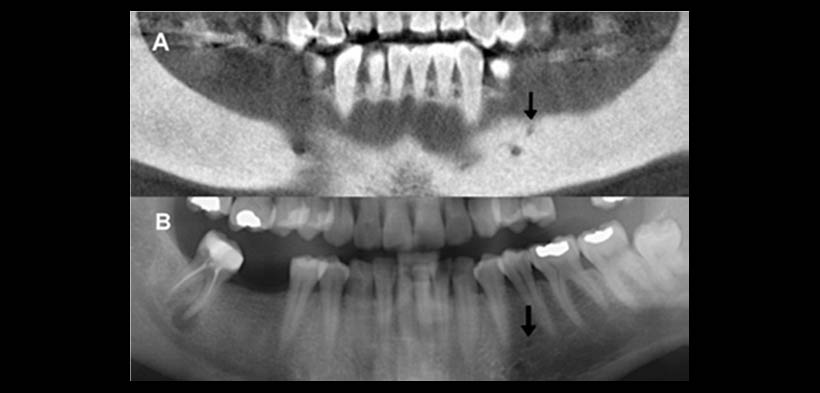

Fig. 2. Foramen mental accesorio utilizando la reconstrucción para-panorámica desde la TC de haz cónico (A). Foramen mental accesorios visualizaron en la correspondiente radiografía panorámica (B).